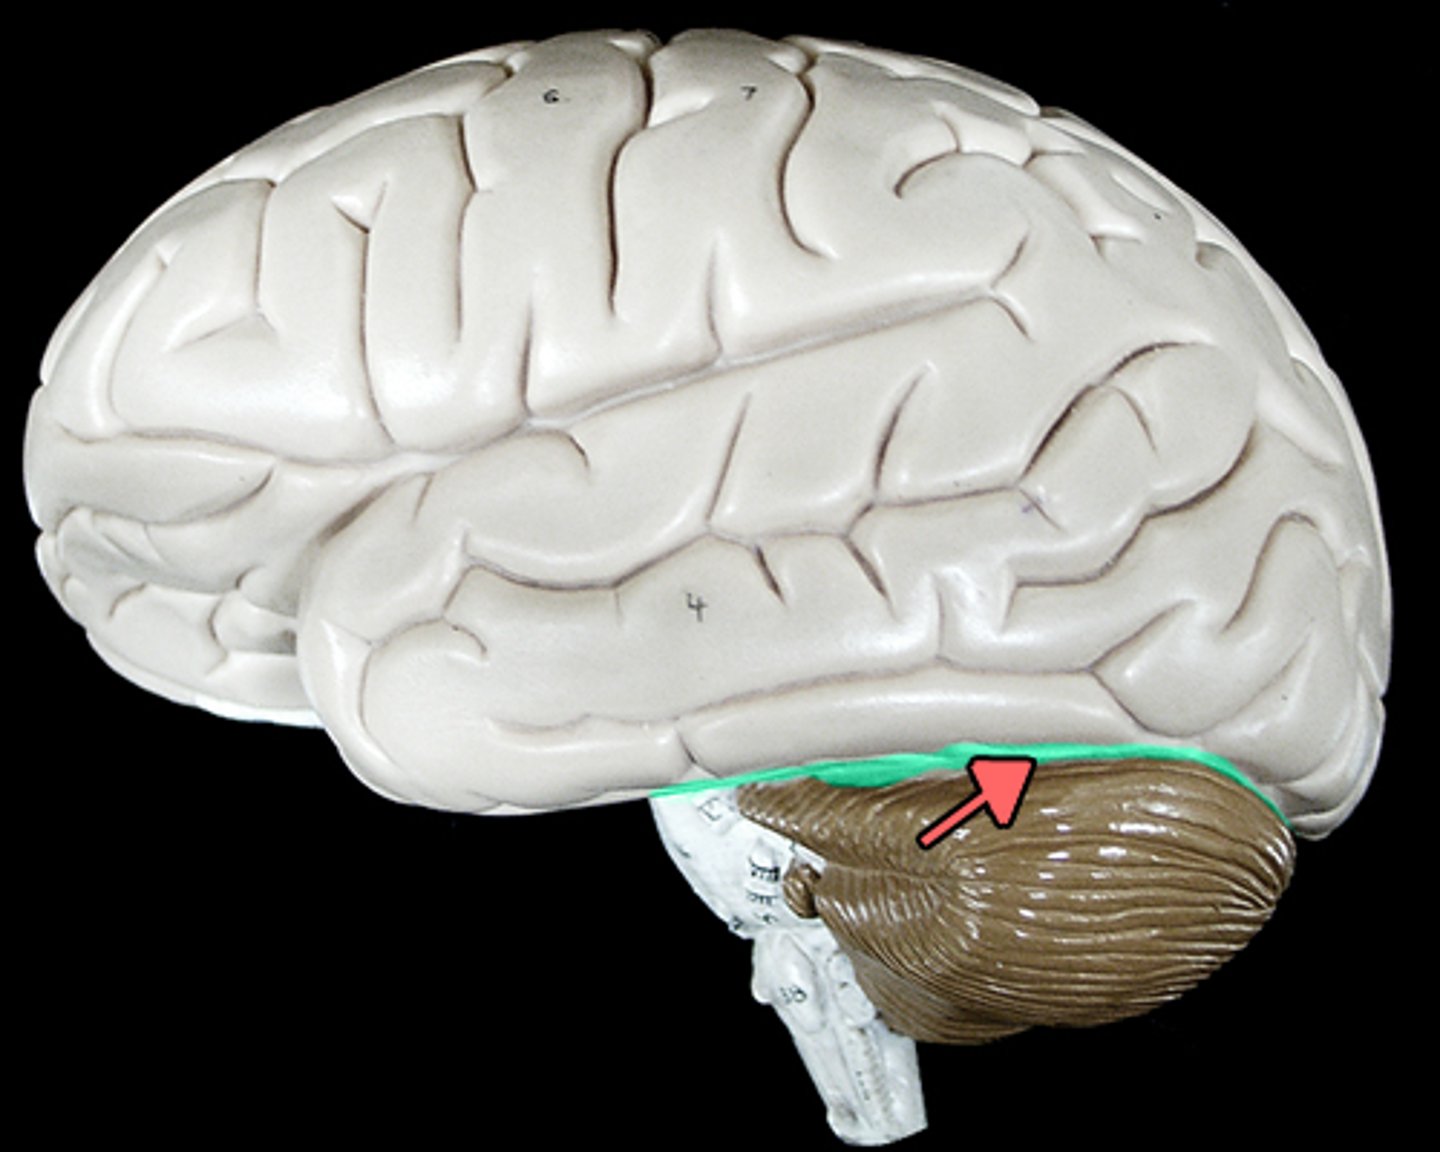

Cerebellum

anterior lobe of cerebellum

posterior lobe of cerebellum

vermis

cerebellar peduncles

folia

arbor vitae

Primary fissure